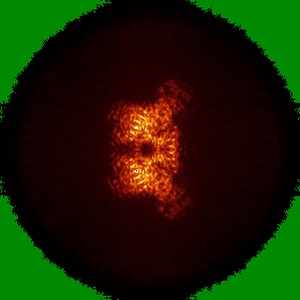

Cryo-EM structure of MPXV core protease in complex with aloxistatin(E64d)

Single-particle2.93 Å